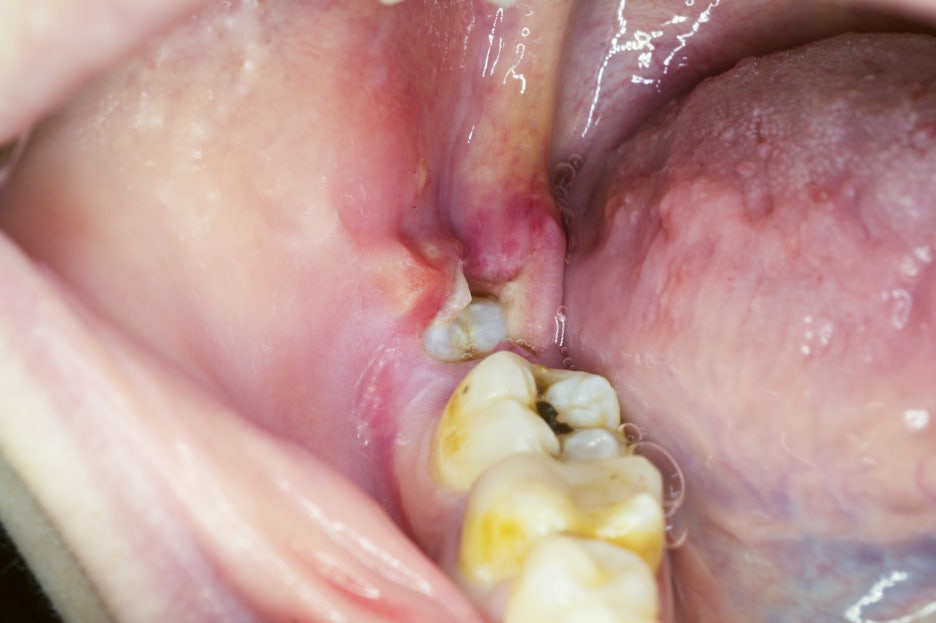

특히 아래 사랑니는 턱뼈 안을 지나가는

신경과 가까운 경우가 많기 때문에

발치 전 정확한 위치 확인이 중요합니다.

특히 매복 사랑니의 경우

치아가 뼈 속에 묻혀 있는 상태이기 때문에

어떤 방향으로 접근할지, 얼마나 힘을 사용할지

세심한 판단이 필요합니다.